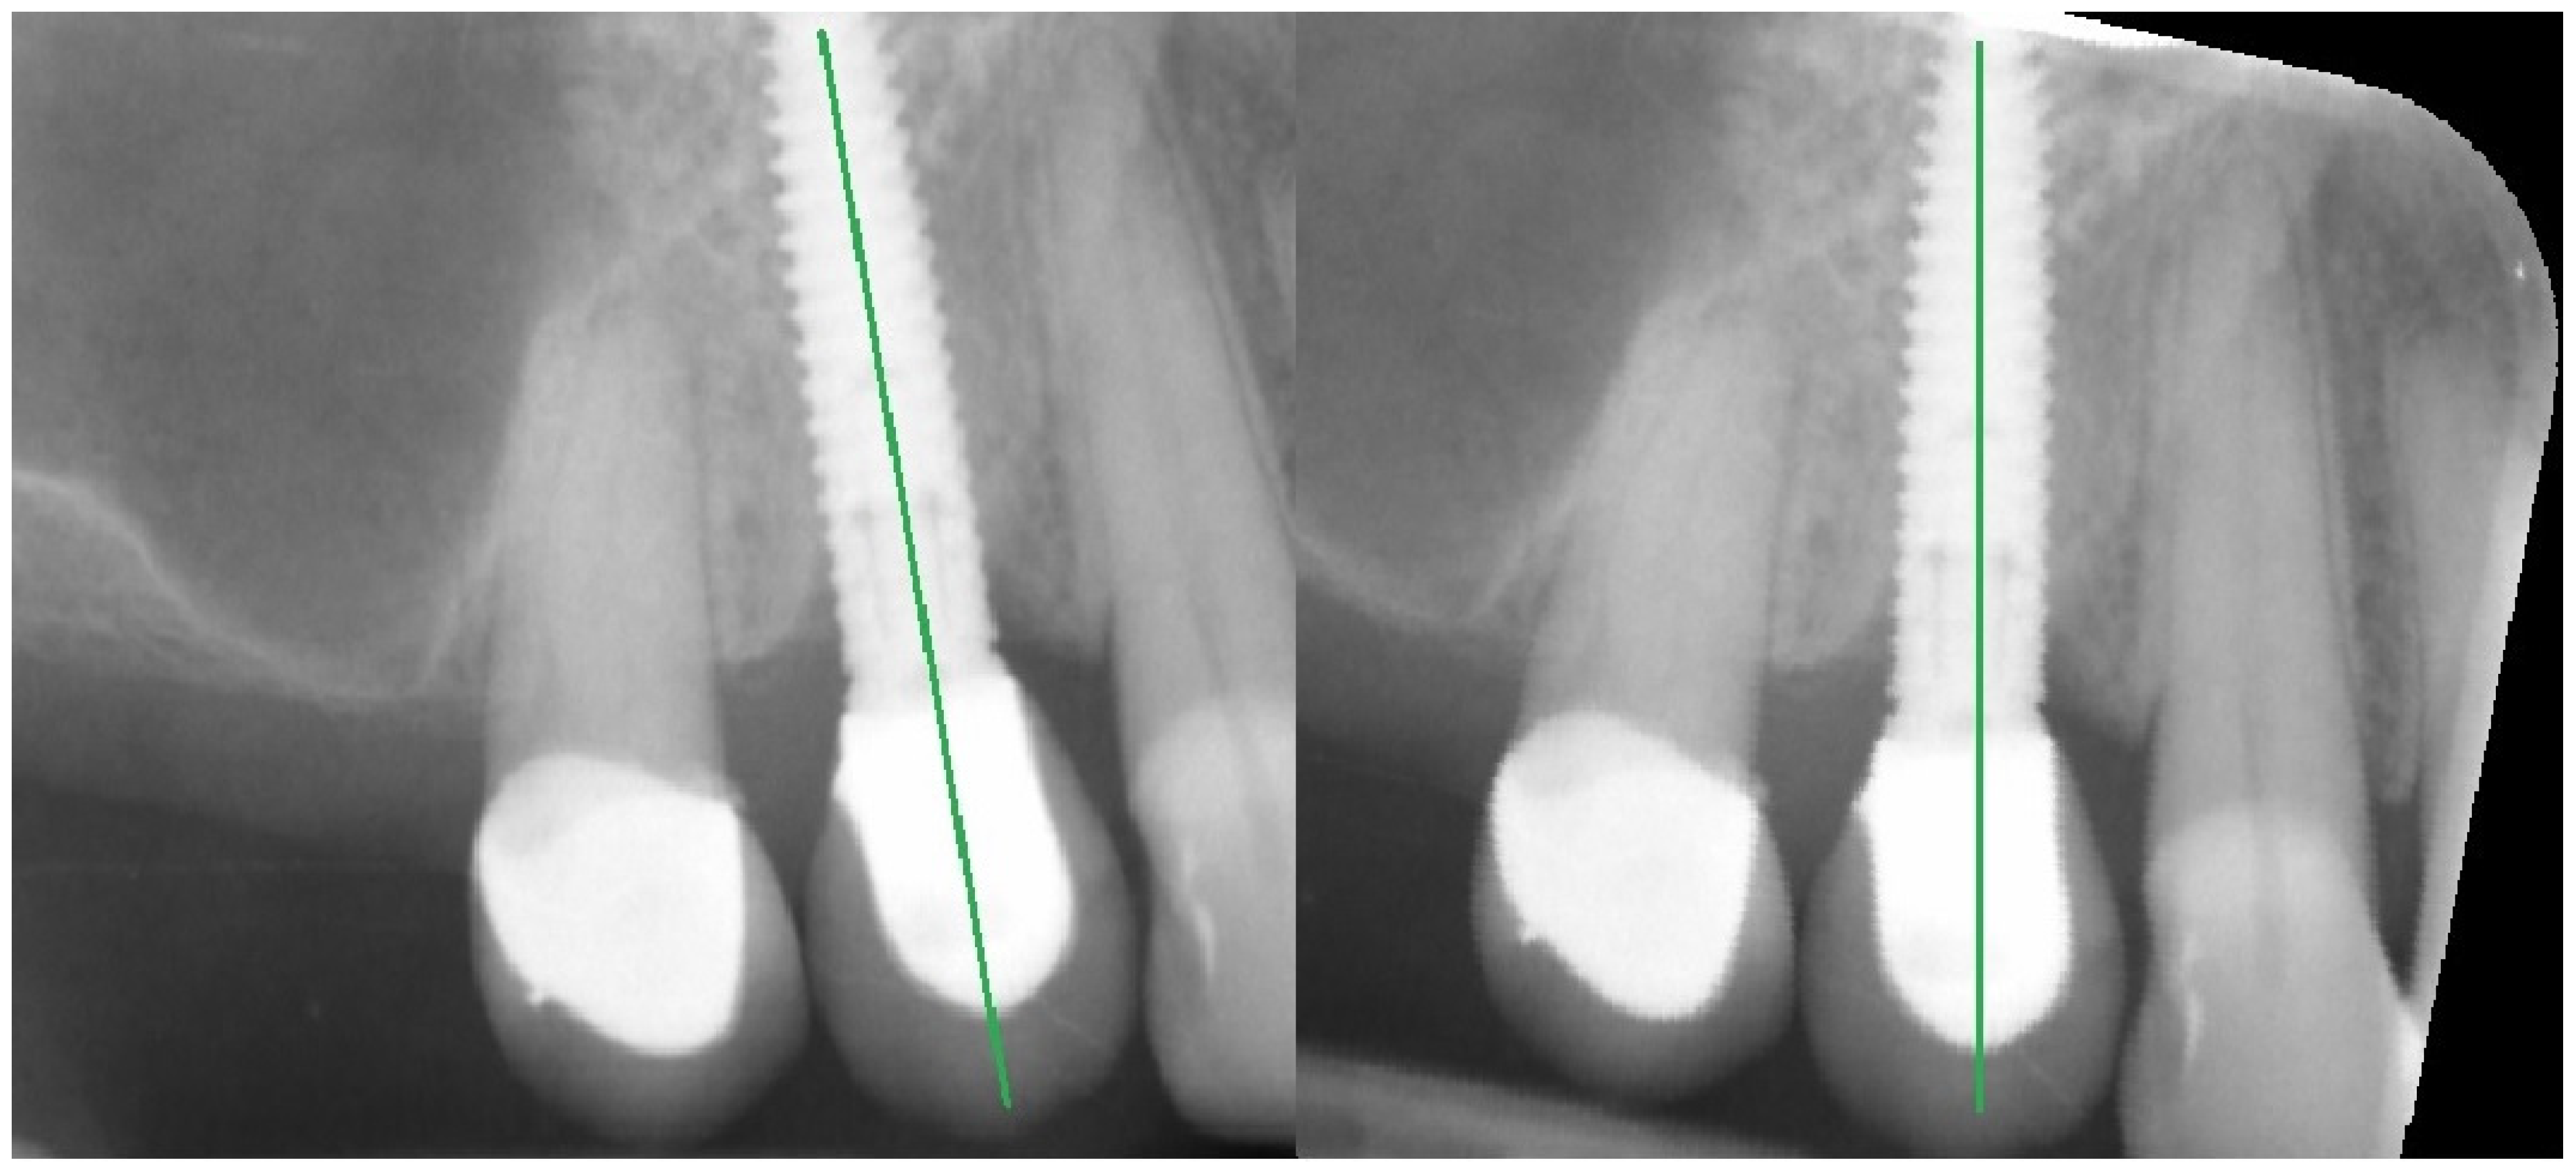

2. Materials and Methods